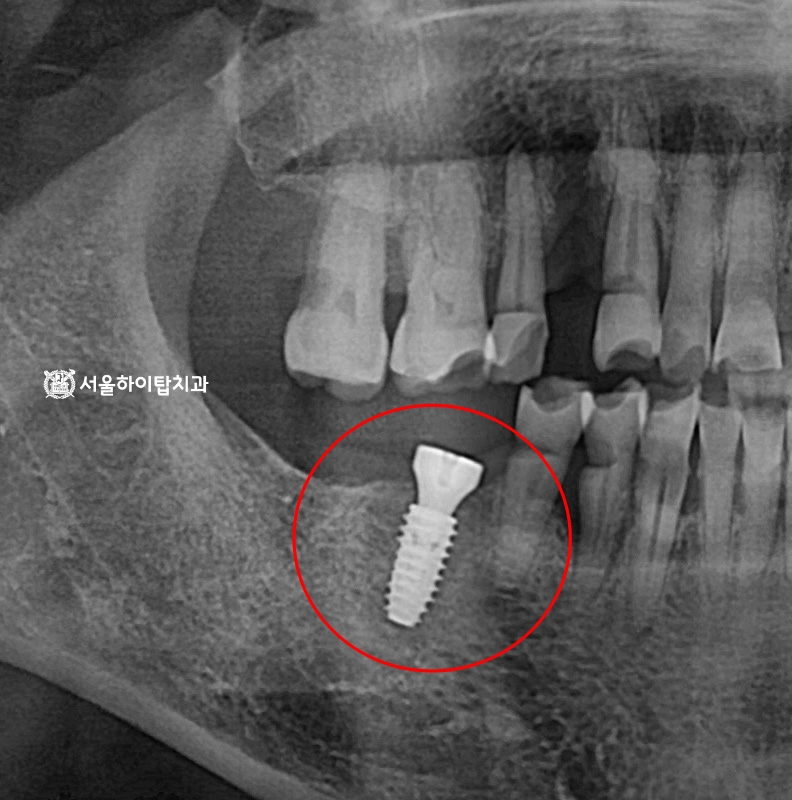

수술 완료

수술이 완료되면, 임플란트와 뼈가 단단히 결합되는

골 유착(osseointegration) 기간을 거치게 됩니다.

이 과정에서 약 한 달 뒤 다시 한 번 엑스레이를 촬영하여,

픽스처의 위치 변동이나 초기 골 유착 상태를 확인하게 됩니다.

이를 통해 식립된 임플란트가 안정적으로 자리잡았는지 평가하고,

이후 최종 보철 제작을 위한 준비를 진행할 수 있습니다.